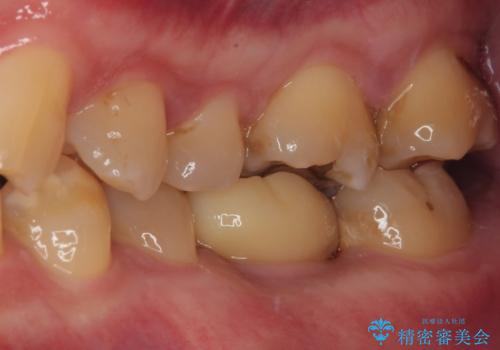

インプラント埋入時に植立具合の安定性を測定したところ、十分な数値が得られたため、速やかに仮歯を装着して咬合回復をさせることができました。

抜歯を含めた外科処置を1回に抑えることができ、あっという間に治療を終えることができました。